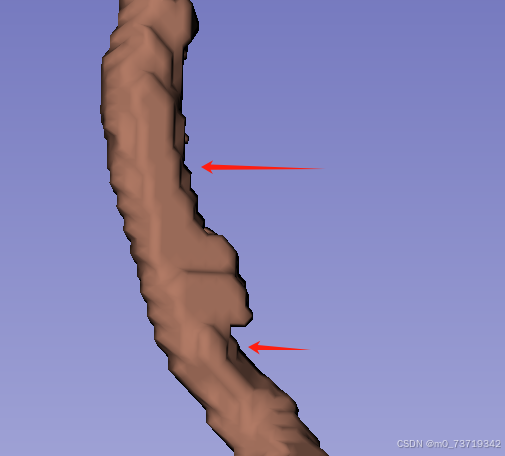

病人dicom数据+.nrrd网络初步分割标签+医生诊断报告(看病变位置)

冠脉辨别如下

网络分割标签顺序(颜色无影响)

2.标注病变(主要为钙化斑块,非钙化斑块,支架)

以诊断结果为标准标注